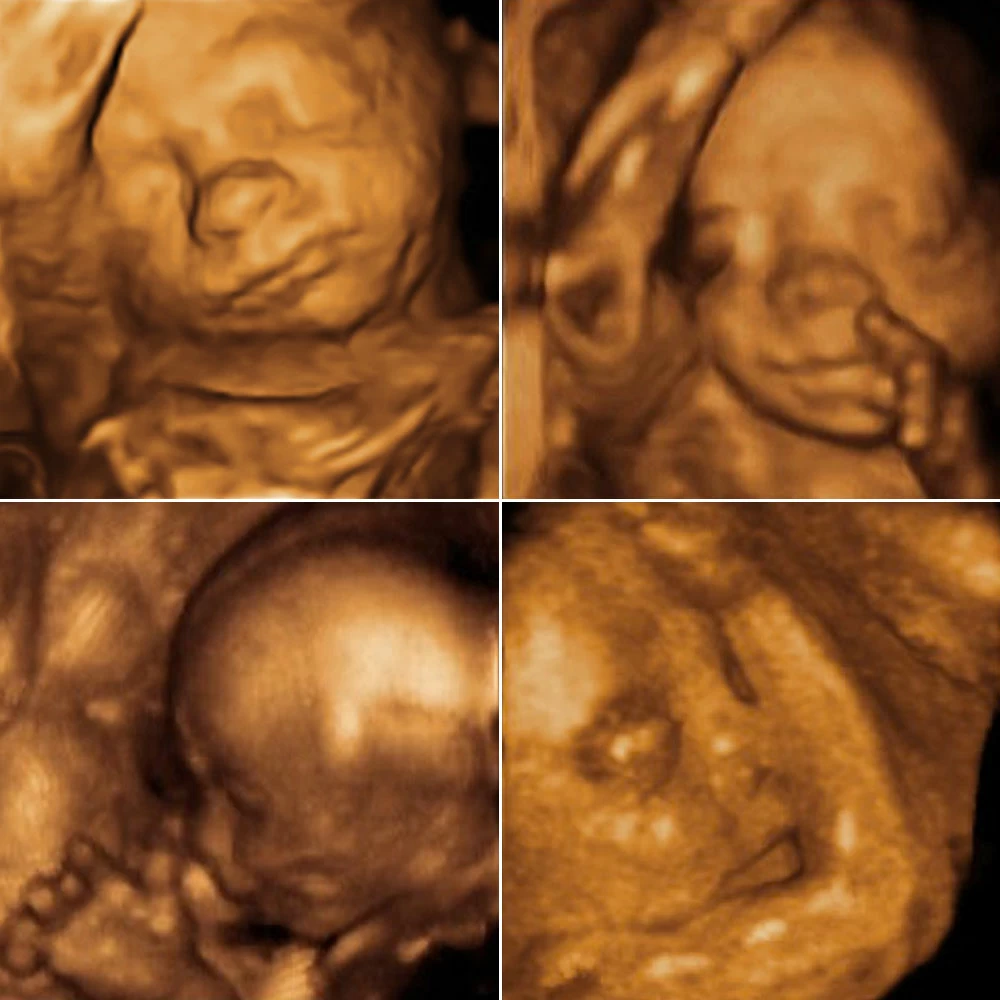

К концу шестнадцатой недели плод уже полностью сформирован, у него есть все органы и системы. Активно работают почки, каждый час в околоплодные воды выделяется небольшое количество мочи.Кожа плода очень тонкая, подкожная жировая клетчатка практически отсутствует, поэтому через кожу просвечивают кровеносные сосуды. Кожа выглядит ярко-красной, покрыта пушковыми волосками и смазкой. Хорошо выражены брови и ресницы. Сформированы ногти, но они покрывают только край ногтевой фаланги.Формируются мимические мышцы, и плод начинает «гримасничать»: наблюдаются нахмуривание бровей, подобие улыбки.

Лицо имеет привычный для человека вид.

Полностью сформированы глаза. Во время сна ребенок закрывает глаза, во время бодрствования глаза открыты, периодически ребенок моргает. Цвет радужки у всех детей одинаковый (голубого цвета), затем после рождения начинает меняться. Плод реагирует на яркий свет сужением или расширением зрачка.

Хорошо развиты органы чувств: ребенок улавливает все звуки, видит яркие цвета, может фокусировать зрение, развиты вкусовые рецепторы.